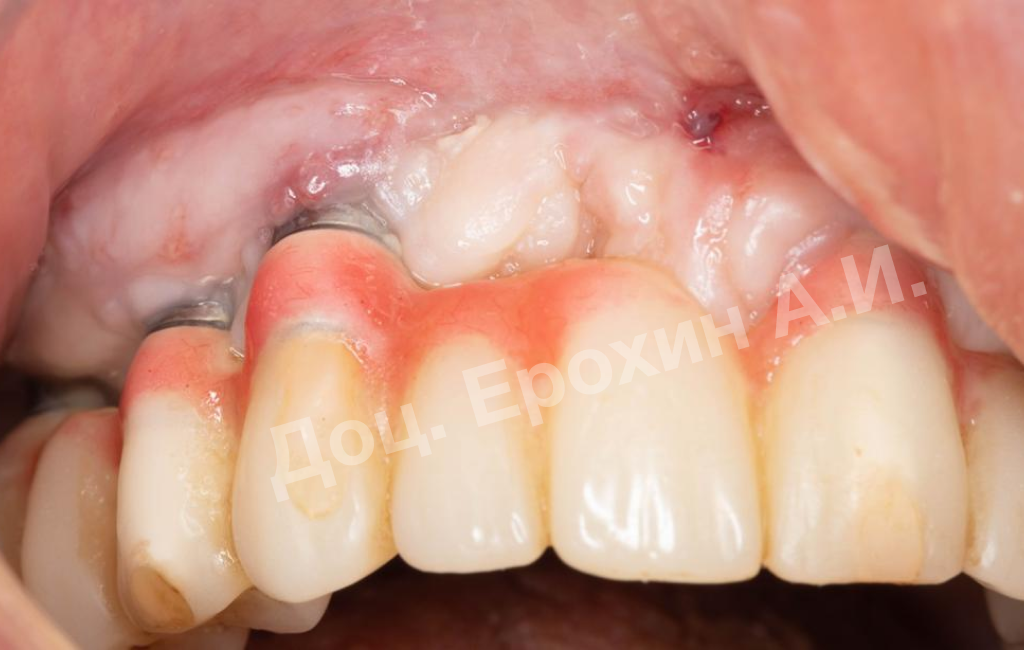

В данном клиническом случае мы можем наблюдать эффект так называемого наползающего прикрепления (creeping attachment), когда десна после удаления момента натяжения начинает сама наплывать на ранее оголенные корни зубов и имплантаты.

На фото видно, что в первом сегменте с 2.5-3 мм оголение корня осталось меньше 1 мм, в области имплантата 21 рецессия самоустранилась, а в области имплантата 26 рецессия до операции была 4.5 мм, а после сократилась до 2 мм.